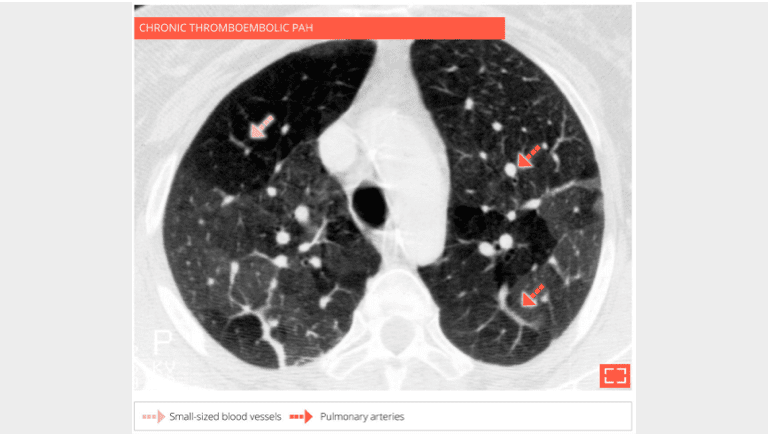

The hypodense regions of the lung contain smaller vessels, the number of which decrease while the size of the pulmonary arteries in dense regions increases corresponding to a redistribution of vascular flow to these perfused regions. A CT scan with injection of contrast agent synchronized to opacification of the pulmonary arteries, must confirm chronic thrombosis of the pulmonary arteries.

The CT scan with contrast medium injection to check for pulmonary artery obstruction shows the small size and distal thrombosis of peripheral pulmonary arteries, confirming chronic thrombosis. Ventilation-perfusion scintigraphy is the recommended exam for screening for these anomalies.